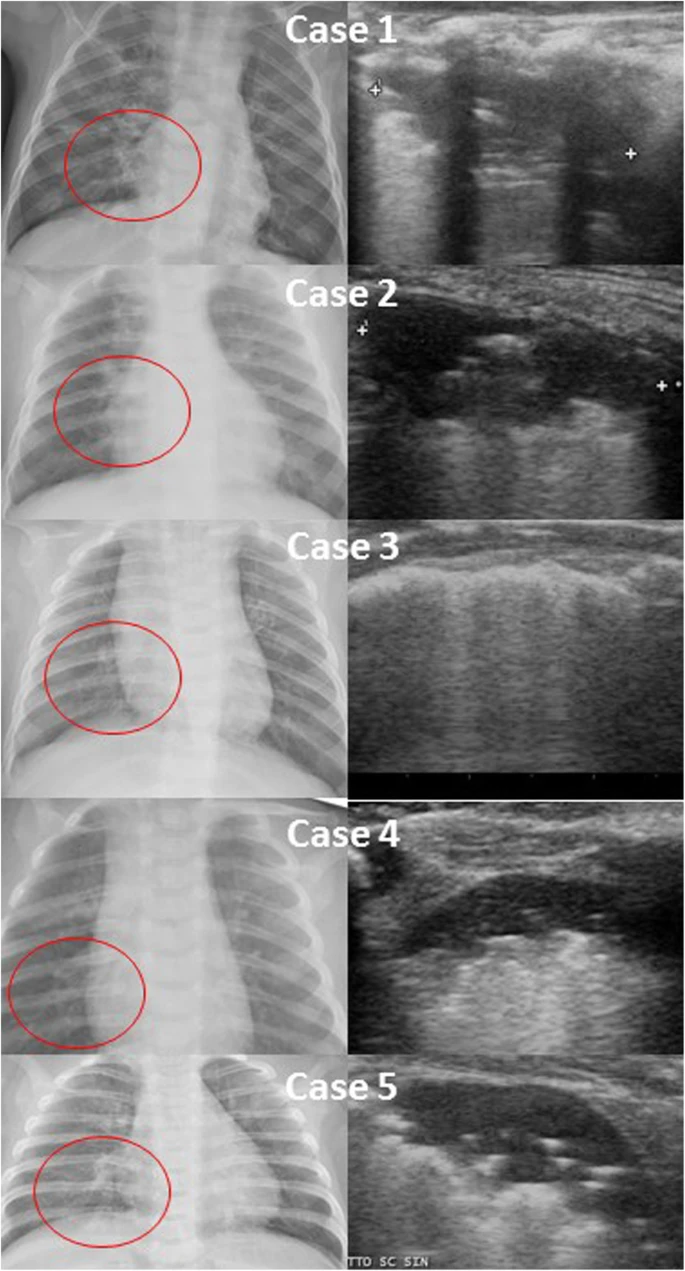

| A case series of paracardiac consolidations on chest X-ray and the corresponding pattern on lung ultrasound, showing posterior, paravertebral, subpleural consolidations |